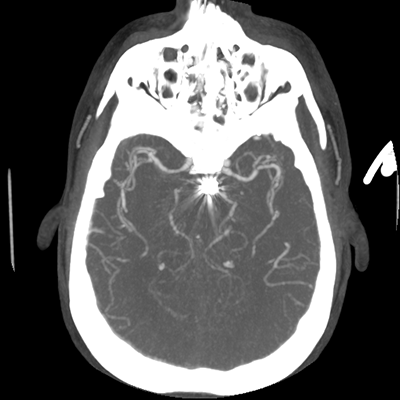

CTA head (MIP)

Starting with the non-contrast head CT, we can appreciate that there's actually not much residual subarachnoid blood at all; it's essentially all resorbed already (and cleared through the EVD). The ventricular caliber is stable. With the CTA head (for convenience's sake, the MIPs were shown), it's subtle, but we can see that the PCAs on each side are not as smooth and regular. The right MCA, starting at the bifurcation, also becomes narrower. This is [radiographic] vasospasm. Now, looking at the CT perfusion-- specifically, the Tmax (MTT) map that were selected-- there's clearly some abnormality within the bilateral cerebellar hemispheres and occipital lobes. Not a lot, but it's there. Delving further into this map, we can appreciate that the areas of abnormality are mainly green, signifying that these areas have Tmax > 6 seconds. This is the threshold that is specific, not sensitive, for vasospasm.

Putting this all together, we have thus identified radiographic vasospasm with the vessel imaging, with perfusion abnormalities that are concordant with it. Does the area of vasospasm and hypoperfusion correlate with the patient's clinical exam?